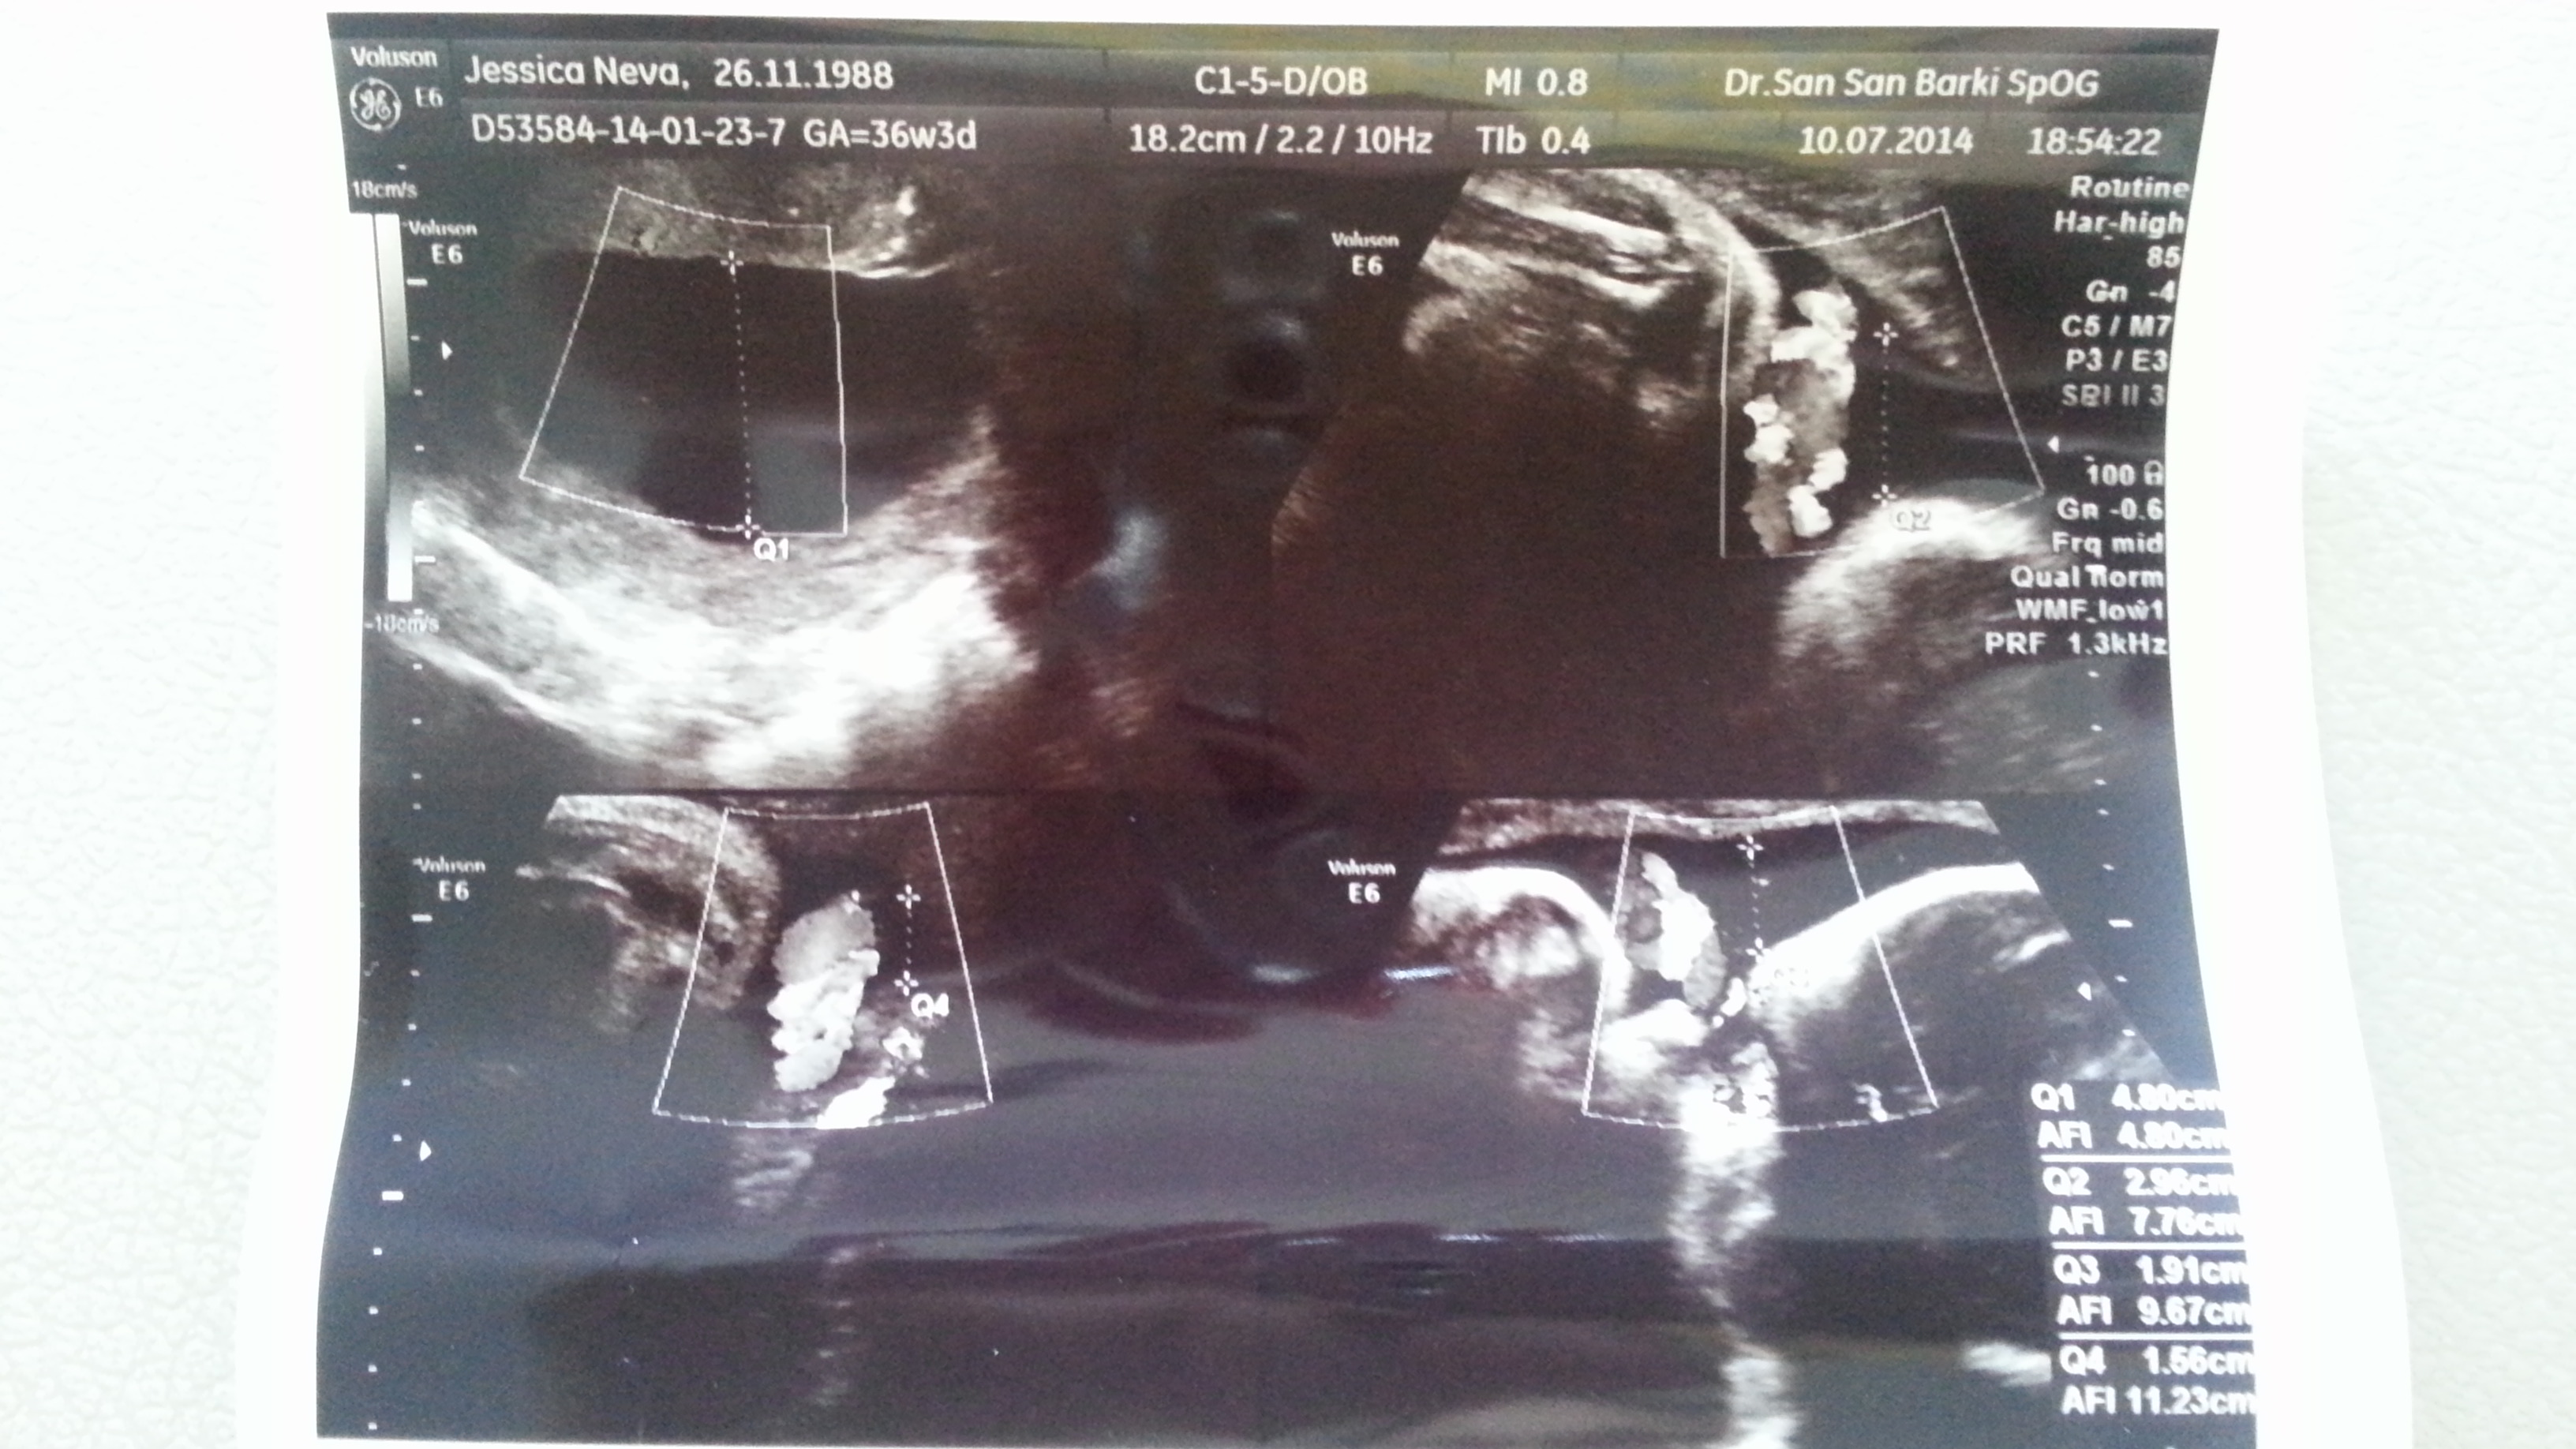

From this week onwards, we will visit our obgyn on a weekly basis. On week 36, the baby’s 2,6 kg and our obgyn’s happy as he wishes the baby to reach 3 kg before labour. His statement surprised us a bit because he never mentioned anything to us before. I just wonder how many more kilograms I will gain until labour as I’ve gained 13 kg up to today!